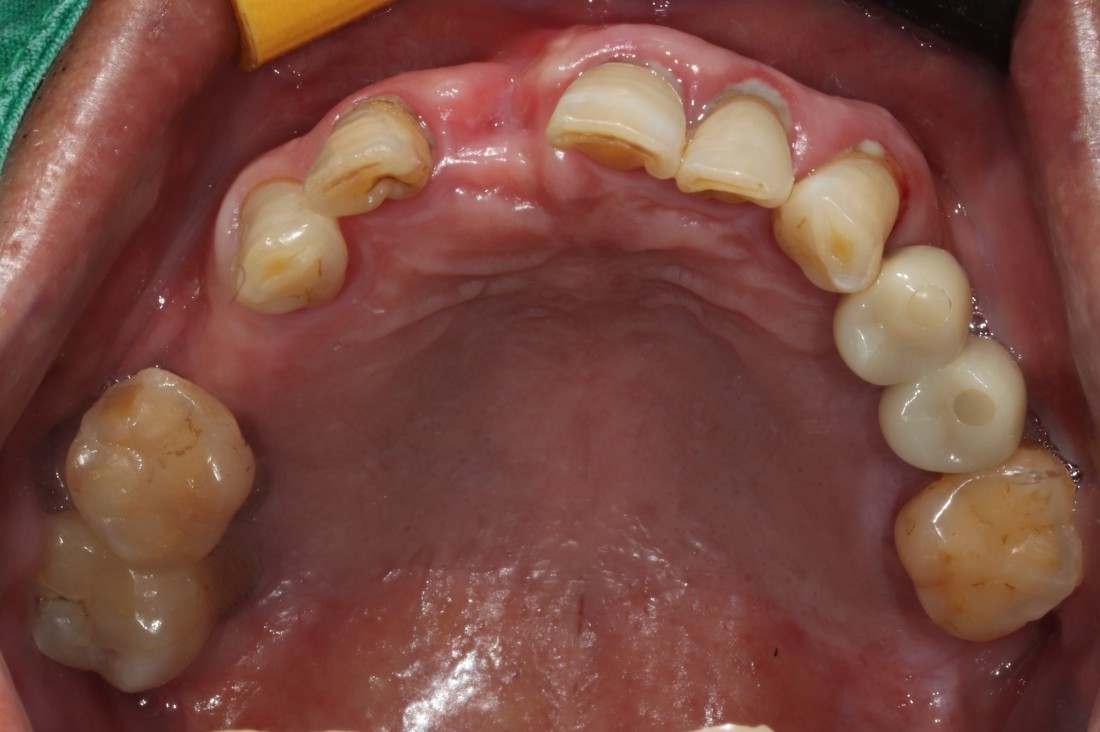

금속재질이 비치는 앞니 임플란트는

이제 작별하세요!

광주 앞니 임플란트 치과에서

화이트어벗을 사용하여

가장 자연스럽게 만듭니다.

또한 광주 앞니임플란트 치과에서는

가장 자연스러운 아름다움을 위하여

앞니 임플란트의 경우 화이트어벗을 사용해

금속 재질이 티나지 않도록

가장 자연치아와 유사하게 시술하고 있습니다.

화이트어벗 및 핑크포세린으로

자연치아와 가장 유사한 색상을 만들며,

튼튼한 고정력과 심미성까지

모두 챙길 수 있는

광주 앞니 임플란트치과입니다.